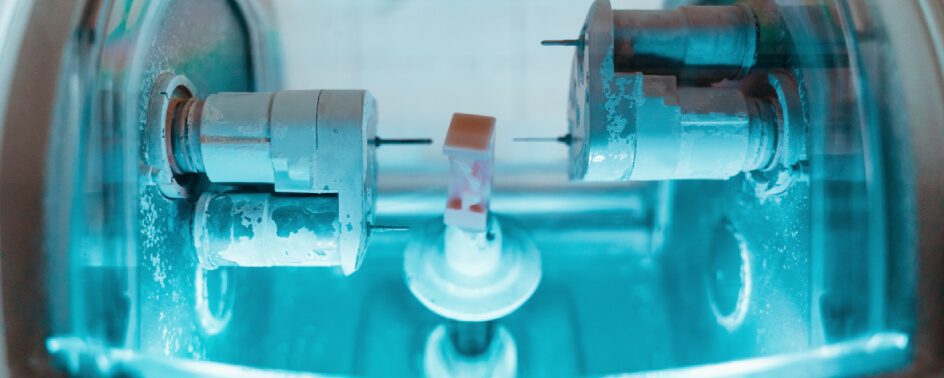

Dental implants are used for several different purposes. Some patients use them as a replacement for natural teeth that are missing due to extractions or trauma, while others will have them placed in order to give structural support and strength to dentures. Dental implants are titanium screws that are placed into the bone and gums […]

Many options exist for filling a gap in your smile caused by a missing tooth. One option that is gaining popularity is dental implant surgery. Dental implant surgery occurs when the dentist places a titanium screw directly into the jawbone. The metal piece then fuses with your jawbone. Next, your mouth is given time to […]